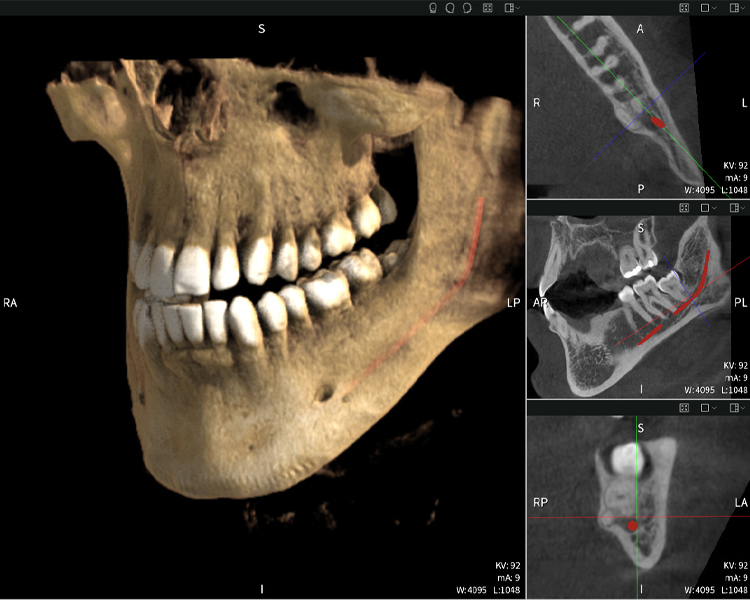

Nachstehend finden Sie einen Fall von Dr. med. dent. Oliver A. Centrella, in dem die CBCT-Aufnahmen mit Seethrough Max entscheidende Informationen zur komplexen Anatomie sowie zur kritischen Beziehung zwischen den Weisheitszähnen und dem Nervus alveolaris inferior lieferten. Bei diesem Fall besteht eine Indikation zur chirurgischen Entfernung der Weisheitszähne.

Abbildungen b–d zeigen verschiedene Ansichten einer 3D-Rekonstruktion des Unterkiefers und bieten eine umfassende Übersicht über die Anatomie des Unterkiefers, die Lage der Nerven im Verhältnis zu den Zähnen und ermöglichen die Beurteilung der Zahnsymmetrie und Ausrichtung.

Abbildung d zeigt den bereits vorbehandelte Zahn 48, dessen Krone entfernt wurde und dessen Wurzeln nahe am Nerv belassen wurden, was das hohe Risiko einer Nervenschädigung verdeutlicht.